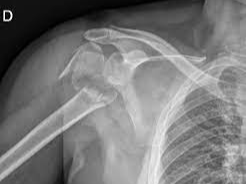

어깨뼈 골절은 어깨 주변을 구성하는 여러 뼈 중 하나가 부러지는 상태를 의미합니다. 어깨는 단순한 관절이 아니라 여러 뼈와 인대, 근육이 복합적으로 연결된 구조이기 때문에 골절의 종류도 다양하게 나타납니다. 흔히 발생하는 골절 위치는 견갑골, 쇄골, 상완골 근위부입니다. 특히 낙상 사고나 교통사고에서는 상완골 근위부 골절이 자주 발생합니다.

이 중에서도 상완골 근위부 골절은 고령자 낙상 사고에서 매우 흔하게 나타나는 골절이며, 경우에 따라 금속 핀이나 금속 플레이트를 이용한 고정 수술이 필요할 수 있습니다.

어깨 골절 중에서도 상완골 골절은 치료 방식에 따라 입원 기간이 달라집니다. 단순 골절이라면 입원 없이 외래 치료로 진행되는 경우도 있지만, 금속 핀이나 금속판을 이용한 고정 수술을 시행하면 입원이 필요합니다.